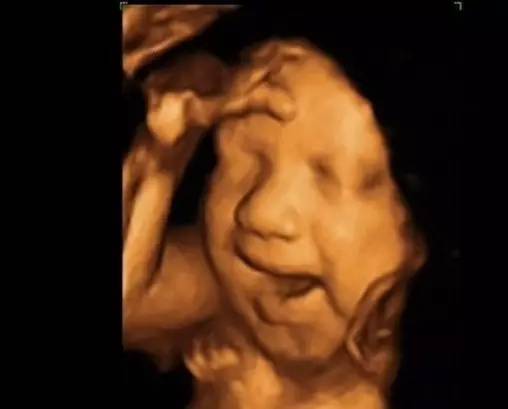

胎儿产前筛查出的异常中,除了明确的组织结构畸形外,还有一部分比较特殊的异常提示,它们不会影响胎儿各个组织系统的正常发育,只是某些超声提示有部分染色体异常的可能,记住了,只是可能,不是一定。

这些异常我们叫它“软指标”,包括:侧脑室增宽、室管膜下囊肿、左心室强光点、双肾盂轻度分离、鼻骨未显示或短小、NT或NF增厚、肠管回声增强、脐带囊肿等等。

1.双肾盂轻度分离:其在绝大部分情况下是胎儿期的正常表现,这种情况在男宝多见,只有在很多软指标同时出现,稍带上它时,它才起到增加染色体异常风险的作用。

2.左心室强光点: 在染色体检查正常的情况下,它的出现没有任何意义,对胎儿没有任何影响,只能说它是顽皮的捣蛋鬼。

3.鼻骨发育不良:鼻骨未显示不等于没有鼻骨,短小不等于鼻骨小,更不等于某些宝妈口中的塌鼻子,大部分是因为胎儿期鼻骨骨化不完全,还是软骨的状态,所以在超声下不显影,它的出现有染色体异常的可能,但不是绝对。

胎儿期的这些异常软指标,只有两个或多个一起出现时,染色体异常的可能性才会增大。某些单独出现时,染色体异常的可能性是很小的,准妈妈们一但遇到这种情况时,不要惊慌,直接放弃宝宝的做法是万万不可取的,应该咨询专业的产前诊断医师,然后下一步进行有必要的胎儿染色体检查,绝大部分宝宝都是正常的,每一个宝宝都是落入凡间的天使,我们不能轻易放弃这些可爱的小精灵们。